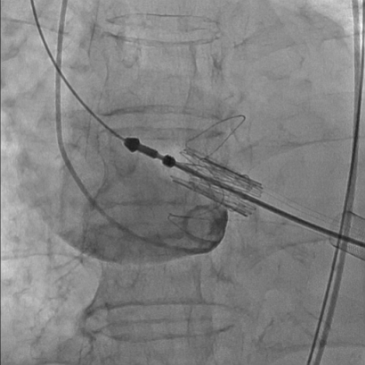

经右侧股静脉置入临时起搏器,经右侧股动脉在患者主动脉无冠窦内放置1根6F猪尾导管协助定位。透视下定位后第五肋间小切口进胸,打开心包,选择心尖裸区缝制六边形荷包。心尖穿刺后将泥鳅导丝过主动脉瓣经升主动脉、主动脉弓到达降主动脉膈肌水平(图1),通过TEE确认细导丝没有与二尖瓣腱索缠绕。单弯管交换硬导丝后(图2、图3),用16F扩张鞘预扩心尖穿刺处,后将 J-Valve瓣膜(29mm)装入输送器。将输送器推送至主动脉根部,释放定位件,适当调整定位件角度使其进入三个主动脉窦部,并通过DSA和TEE确定三个定位件准确入窦后完全释放瓣膜,撤出输送器(图4)。通过DSA和TEE观察人工瓣膜膨胀后金属支架的形态、位置良好,无瓣周漏,收缩期左室侧反流消失(图5、图6)。撤出导丝,收紧心尖处荷包线并打结,后鱼精蛋白中和肝素,彻底止血,逐层关胸,封皮,拔出股动脉鞘并在股动脉穿刺处压迫止血。手术过程顺利,患者生命体征平稳。

图4 释放定位件-定位件入窦-释放瓣膜-撤出输送器和单弯管

图5人工瓣释放后外径约28mm,形态、位置良好

图6 TEE和DSA:人工瓣无瓣周漏

术后DSA显示,与大弯侧相比,主动脉弓小弯侧人工瓣位置较深,这与极度“横位心”,即主动脉角度过大导致的人工瓣膜同轴性不佳有关,尽管术者已经尽可能在释放瓣膜前将其同轴性调到最佳状态。但术后TEE提示人工瓣短轴形态良好,成 “正圆形”强回声,膨胀后最大外径约28mm,表明瓣环周围组织对人工瓣有足够的径向支撑力,瓣膜稳定,证明术前选择29mm人工瓣是正确的。这要求术者对TEE影像具有极致的解读能力和判断力。